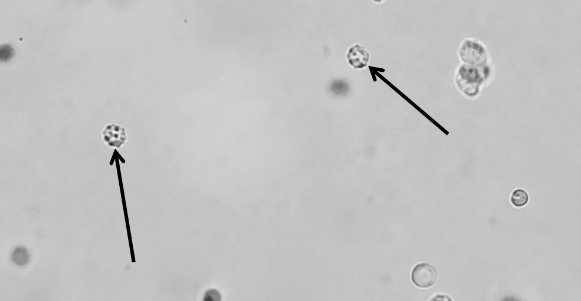

紅細胞